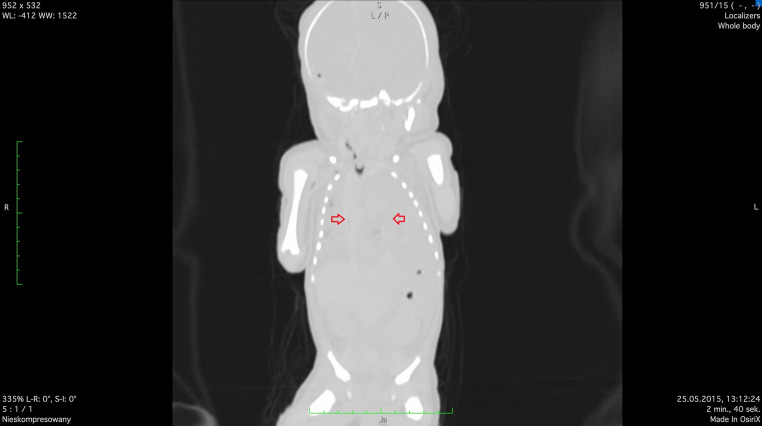

Congenital diaphragmatic hernia is associated with high risk of neonatal death. It is observed in about 1 in 3,000 live births. Fetoscopic tracheal occlusion procedure is a therapeutic option with survival rate 46.4%. Our aim was analysis of the suitability of postmortem computed tomography in the case of neonatal death occurred after fetoscopic endotracheal occlusion performed due to the severe isolated left-sided congenital diaphragmatic hernia. Postmortem computed tomography can be helpful in such cases because it allows for an objective assessment of whether the procedures used after the birth of the newborn enabled effective lung ventilation. Our case was the first use of postmortem computed tomography in neonatal death after fetoscopic endotracheal occlusion worldwide.

Abstract Image